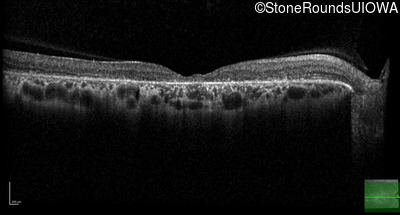

Optical Coherence Tomography - Left - 20/60

Exemplar / OCT Stack